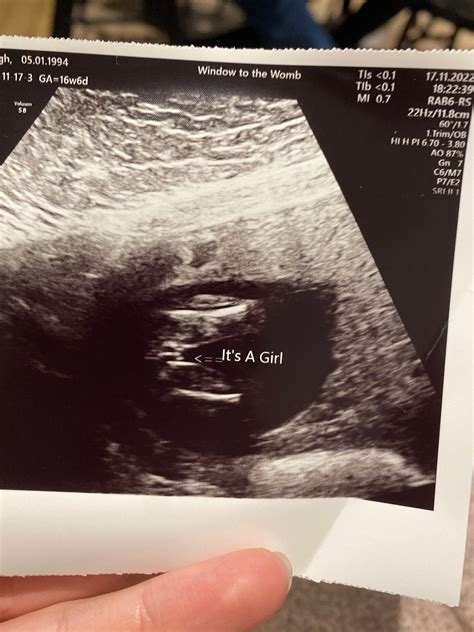

• Ultrasound: Uses sound waves to create images and is generally considered safe during pregnancy.

Before considering a CT scan while pregnant, healthcare providers often explore alternative imaging methods that do not involve ionizing radiation. These include:

If these alternatives are not sufficient, the healthcare provider may proceed with a CT scan, taking precautions to minimize radiation exposure.